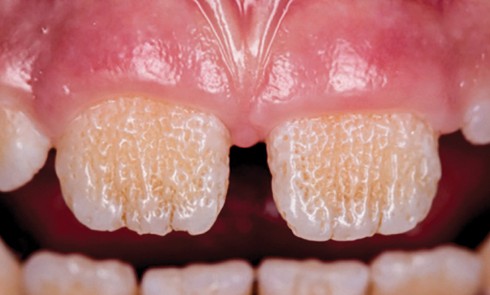

Amélogenèse imparfaite

Définition L’amélogenèse imparfaite est le nom donné à un groupe hétérogène de pathologies caractérisées par un défaut inné du développement...

L’amélogenèse imparfaite (AI) est une anomalie héréditaire rare de la structure dentaire, caractérisée par des défauts amélaires en denture temporaire...

Une pathologie est dite rare lorsqu’elle affecte moins d’un individu sur 2 000 dans une population. Les amélogenèses imparfaites héréditaires (AIH)...